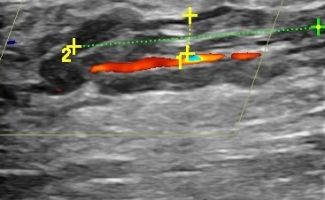

Με το Triplex Αρτηριών Κάτω Άκρων μπορούμε να αξιολογήσουμε αν υπάρχει παθολογία στις αρτηρίες. Συνήθεις παθολογίες στις αρτηρίες είναι τα ανευρύσματα και οι στενώσεις. Με το Triplex μπορούμε να υπολογίσουμε με ακρίβεια το βαθμό στένωσης στις αρτηρίες και να διαπιστώσουμε αν υπάρχει απόφραξη. Η δυνατότητα διάγνωσης παθολογιών στις αρτηρίες των κάτω άκρων με τη χρήση του Triplex είναι πολύ χρήσιμη για την αντιμετώπιση αγγειακών προβλημάτων, καθώς πρόκειται για παθήσεις που μπορούν να οδηγήσουν σε σοβαρές συνέπειες αν δεν ανιχνευθούν έγκαιρα.